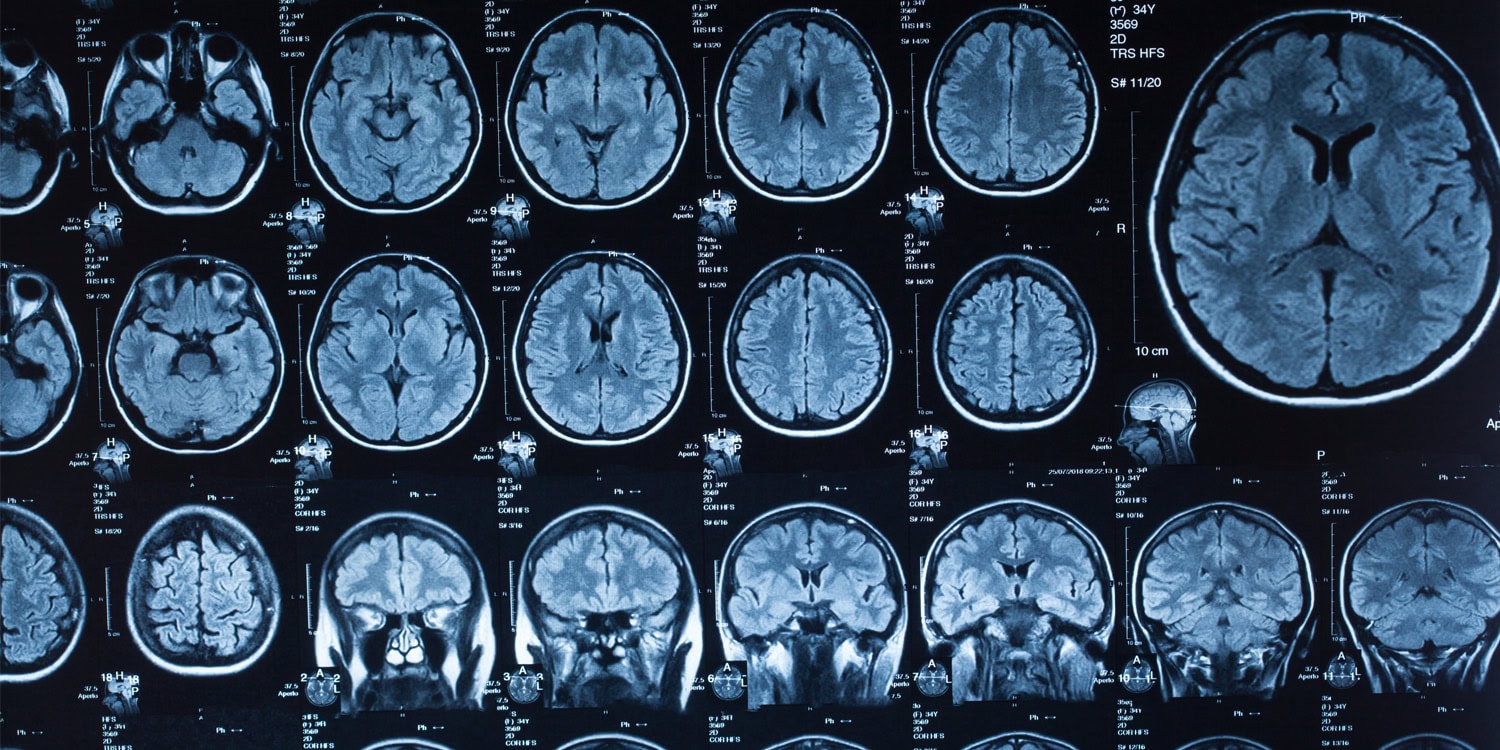

Zaawansowane MRI pokazało, że doświadczeni medytujący potrafią wpływać na krążenie płynów w mózgu. To może być klucz do naturalnego wspomagania systemu oczyszczania.